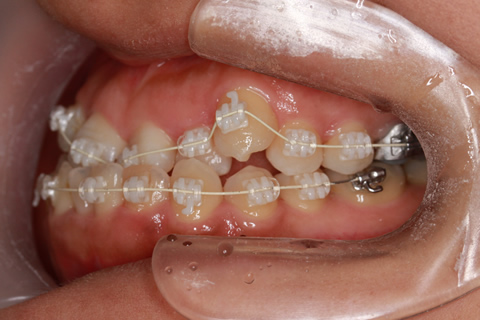

受け口(反対咬合)の症例

症例一覧